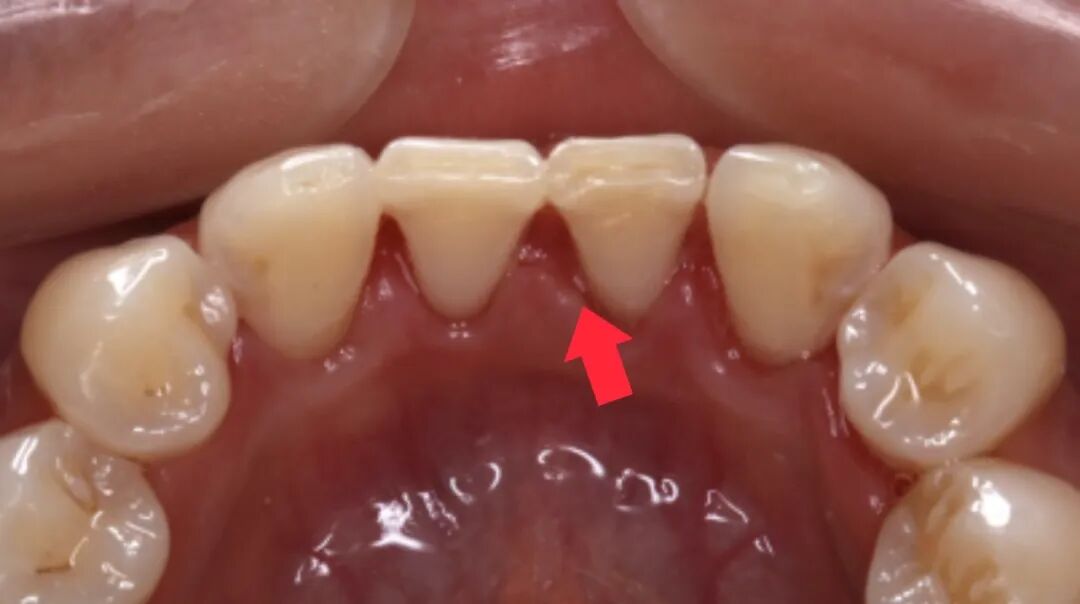

牙龈健康的恢复:炎症消退

如果在治疗前,你的牙龈因为炎症而肿胀,这种肿胀会暂时“遮住”一部分牙缝。在治疗后,随着炎症消退,牙龈会恢复到健康状态并贴合在牙齿表面,这时牙缝也会显得更加明显。

治疗前

治疗后